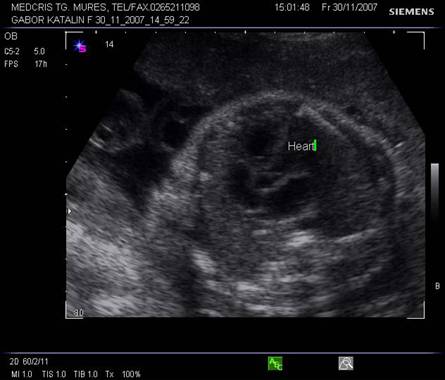

Fig. nr. 179. Planul 3 de sectiune a cordului evidentiaza plecarea trunchiului pulmonarei ( sageata ) din ventricului drept